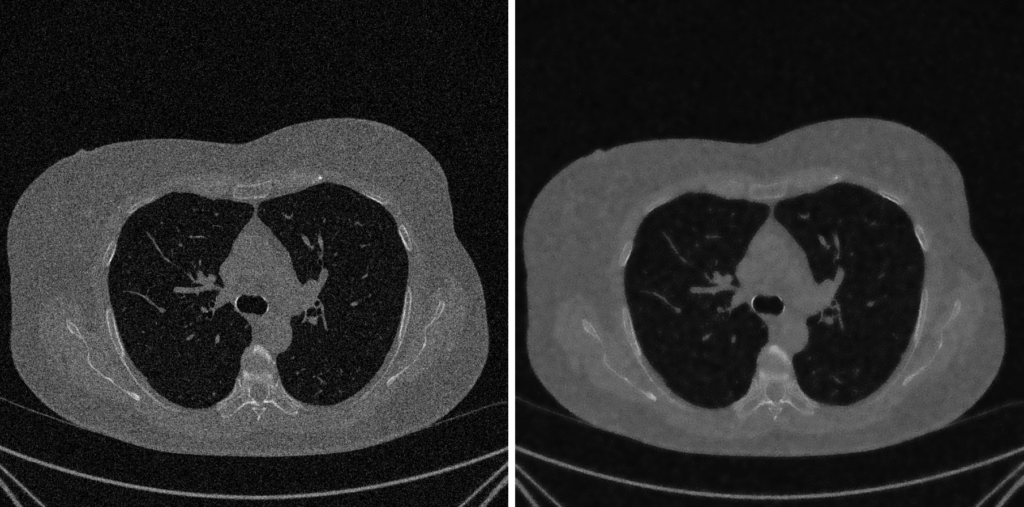

4. Fase 3: Denoising e Sharpening

Dopo aver corretto gli artefatti sistematici, l’immagine è corretta, ma non ancora pulita. Può essere ancora affetta da rumore casuale (elettronico o statistico), che oscura i dettagli fini e complica le analisi successive come la segmentazione.

Esploriamo ora due operazioni complementari e in apparente conflitto: il Denoising (ridurre il rumore) e lo Sharpening (evidenziare i bordi).

1. Denoising: Smussare il Rumore, Preservare il Segnale

L’obiettivo è sopprimere il rumore senza distruggere i bordi e le texture reali dell’immagine.

2. SSIM (Structural Similarity Index): il Radiologo

L’SSIM è una metrica moderna e percettiva, progettata per imitare il modo in cui un essere umano (come un radiologo) giudica la qualità di un’immagine.

- Cosa Misura: La somiglianza strutturale. L’SSIM riconosce che l’occhio umano è molto più bravo a percepire strutture e relazioni tra i pixel che a notare piccoli errori numerici.

- Come funziona: Invece di confrontare singoli pixel, confronta piccole finestre (patch) di immagine, valutando tre componenti chiave:

- Luminanza: Il livello medio di intensità è simile?

- Contrasto: La varianza locale dei dettagli è simile?

- Struttura: Il pattern dei pixel (quindi la loro correlazione) è simile?

- Obiettivo: Massimizzare l’SSIM (il cui valore va da -1 a 1, dove 1 è identità perfetta).

Conclusione: Il Trade-Off Diagnostico

Qui sta il punto cruciale dell’intero imaging scientifico:

Un PSNR alto non significa sempre un’immagine diagnosticamente migliore.

Immaginiamo un filtro di denoising molto aggressivo (es. un forte blur Gaussiano). Questo filtro “spalma” il rumore, riducendo drasticamente l’errore numerico (l’MSE) e portando a un PSNR altissimo.

Tuttavia, nel processo, quel filtro ha anche “spalmato” una micro-lesione o una linea di frattura sottile. Ha distrutto la struttura.

- PSNR: Alto (il matematico è felice, l’errore medio è basso).

- SSIM: Basso (il radiologo è scontento, il dettaglio strutturale è perso).

- Valore Diagnostico: Nullo.

Il vero obiettivo dello sviluppo di algoritmi (come NLM o Wavelet Denoising) non è massimizzare ciecamente il PSNR, ma trovare il perfetto trade-off: un algoritmo che riduca il rumore (aumentando il PSNR) preservando al contempo i dettagli critici (mantenendo alto l’SSIM).